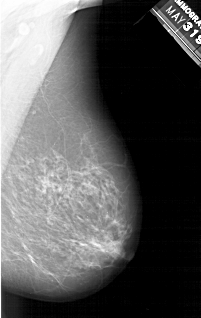

A_1214_1.LEFT_MLO

LEFT_MLO LINES 6871 PIXELS_PER_LINE 3511 BITS_PER_PIXEL 12 RESOLUTION 43.5 OVERLAY